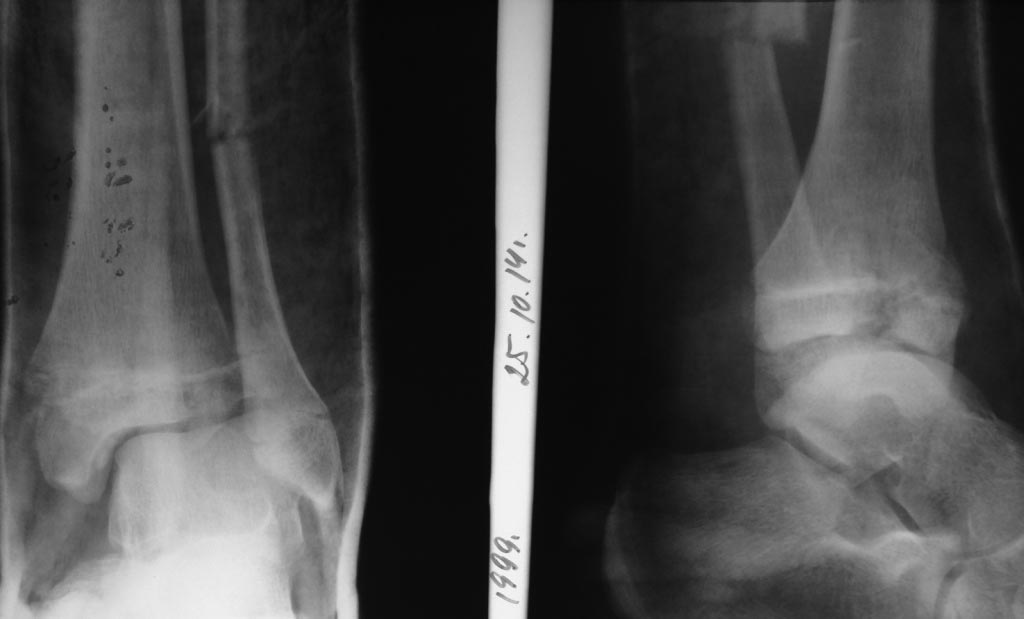

Ребенок 15 лет. Госпитализирован 25.10.14. Репозиция, затем гипс,

закономерная смена его на вытяжение в связи с появлением фликтен.

Имя     : 2 после репозиции.JPG

Тип     : image/jpeg

Размер  : 50383 байтов